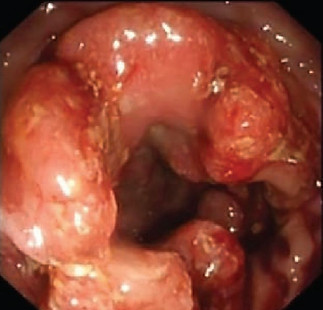

This complex operation is ​usually used for lower rectal cancers. (such as the one in the image) Rectal cancer is a disease with complex decision making that Prof Gilmore will guide you through. Depending on the size, location and MRI scan appearance of your cancer Prof Gilmore will carefully guide you through the modern decision making for this disease.

Most patients with rectal cancer expect an operation as the first treatment. This is true for relatively early cancers. However the majority of patients will be advised either chemotherapy first (to treat the whole body and the rectal tumour) and then radiotherapy. Some are advised to have radiotherapy[y first